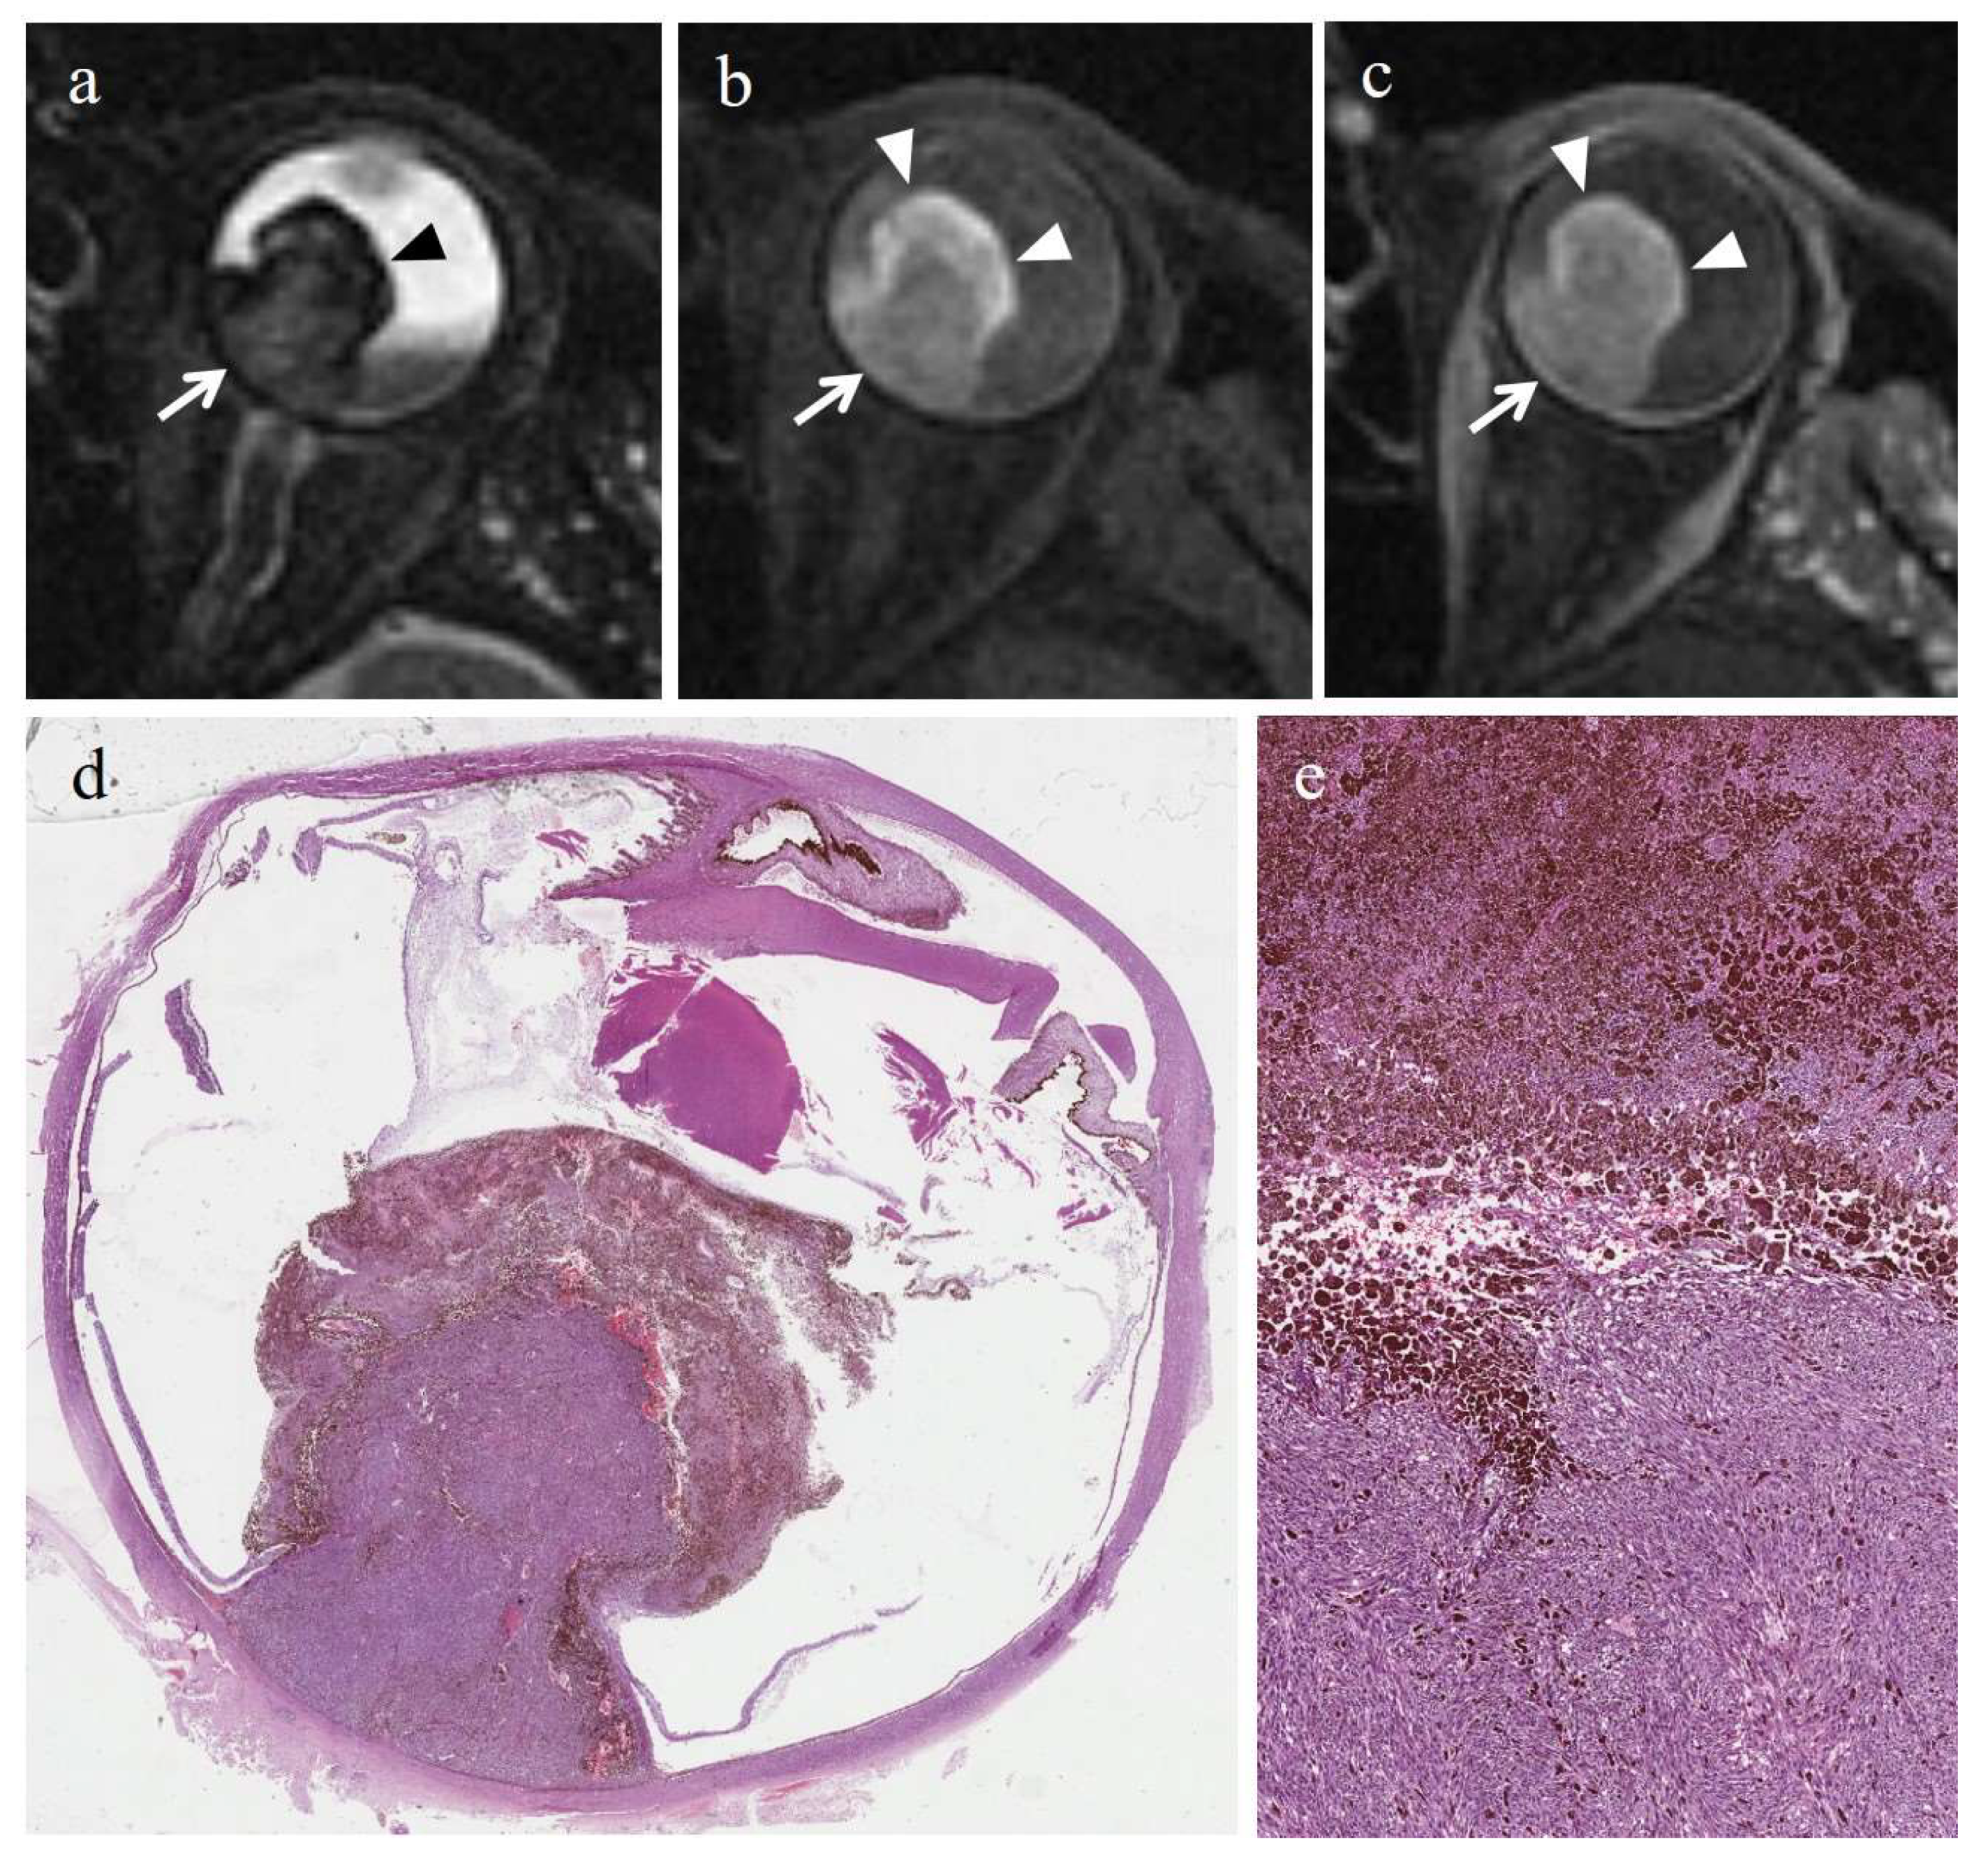

3.2.2. Histopathologic Findings in the Control Group

3.3.2. MRI Findings in the Control Group

| Patient | Histologic Type | Degree of Pigmentation | Degree of Necrosis | Necrotic Pattern |

|---|---|---|---|---|

| 1 | Epithelioid cell | Pigmented | Grade I | Multiple foci- hemorrhagic/coagulative-type, tumor necrosis |

| 2 | Epithelioid cell | Poorly pigmented | Grade I | Multiple foci- hemorrhagic/coagulative-type, tumor necrosis |

| 3 | Spindle cell | Pigmented | Grade II | Multiple foci tumor necrosis |

| 4 | Mixed cell type | Pigmented | Grade I | Multiple foci tumor necrosis |

| 5 | Spindle cell | Pigmented | Grade I | Multiple foci- hemorrhagic/coagulative-type, tumor necrosis |

| 6 | Mixed cell type | Poorly pigmented | Grade I | Multiple foci- hemorrhagic/coagulative-type |

| Patient | T2 | T1 | Gd-T1 | DWI | ADC × 10−3 mm2/s ** |

|---|---|---|---|---|---|

| 1 | - | - | - | - | 1.04 |

| 2 | - | - | - | - | 1.22 |

| 3 | - | - | - | - | 0.63 |

| 4 | - | - | - | - | 0.78 |

| 5 | - | - | - | - | 1.05 |

| 6 | Hyperintense | Hypointense | No enhancement | No restriction | 0.80 |